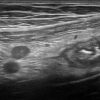

Viêm ruột

» Thông tin: Nữ giới – 18 tuổi.

» Lâm sàng: Tiêu chảy.